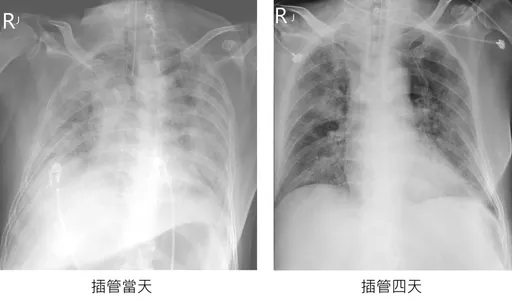

...峰透过脸书指出,一位从中国回来的台商,3天就出现「大白肺」,即严重肺炎的病征,因此插管、陷入病危,但...

...己快筛验出确诊,从X光片显示,患者已呈现严重肺炎的大白肺,他直言「如果没有赶回来留在中国应该是死路一...

苏一峰在脸书发文表示,「大白肺台商稳定了!👍台湾医护人员就是强!」好消息令众人振奋,但时常位医护人员...

...,北市联医胸腔内科医师苏一峰7日在脸书PO出一张「大白肺」X光片,表示一名60岁台商返台后3天确诊,...

...一名刚从中国返台的确诊台商,胸部X光竟是严重肺炎的大白肺,他并惊爆隔离床位告急,今天本土确诊白肺插管...